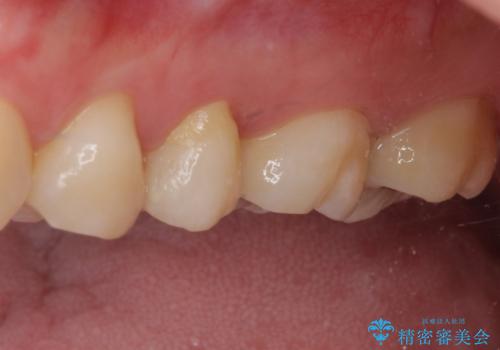

その後、左上の奥歯にも咬合時の痛みが認められ、レントゲン写真より歯内の神経が失活していることが分かりました。

2歯ともに根管治療を行い、その後はオールセラミッククラウンにて補綴治療を行うこととしました。

来院時には食事が取れないほどの痛みを訴えていらっしゃいましたが、処置後からは痛みが軽減され、食事もいつも通りに取れるようになりました。